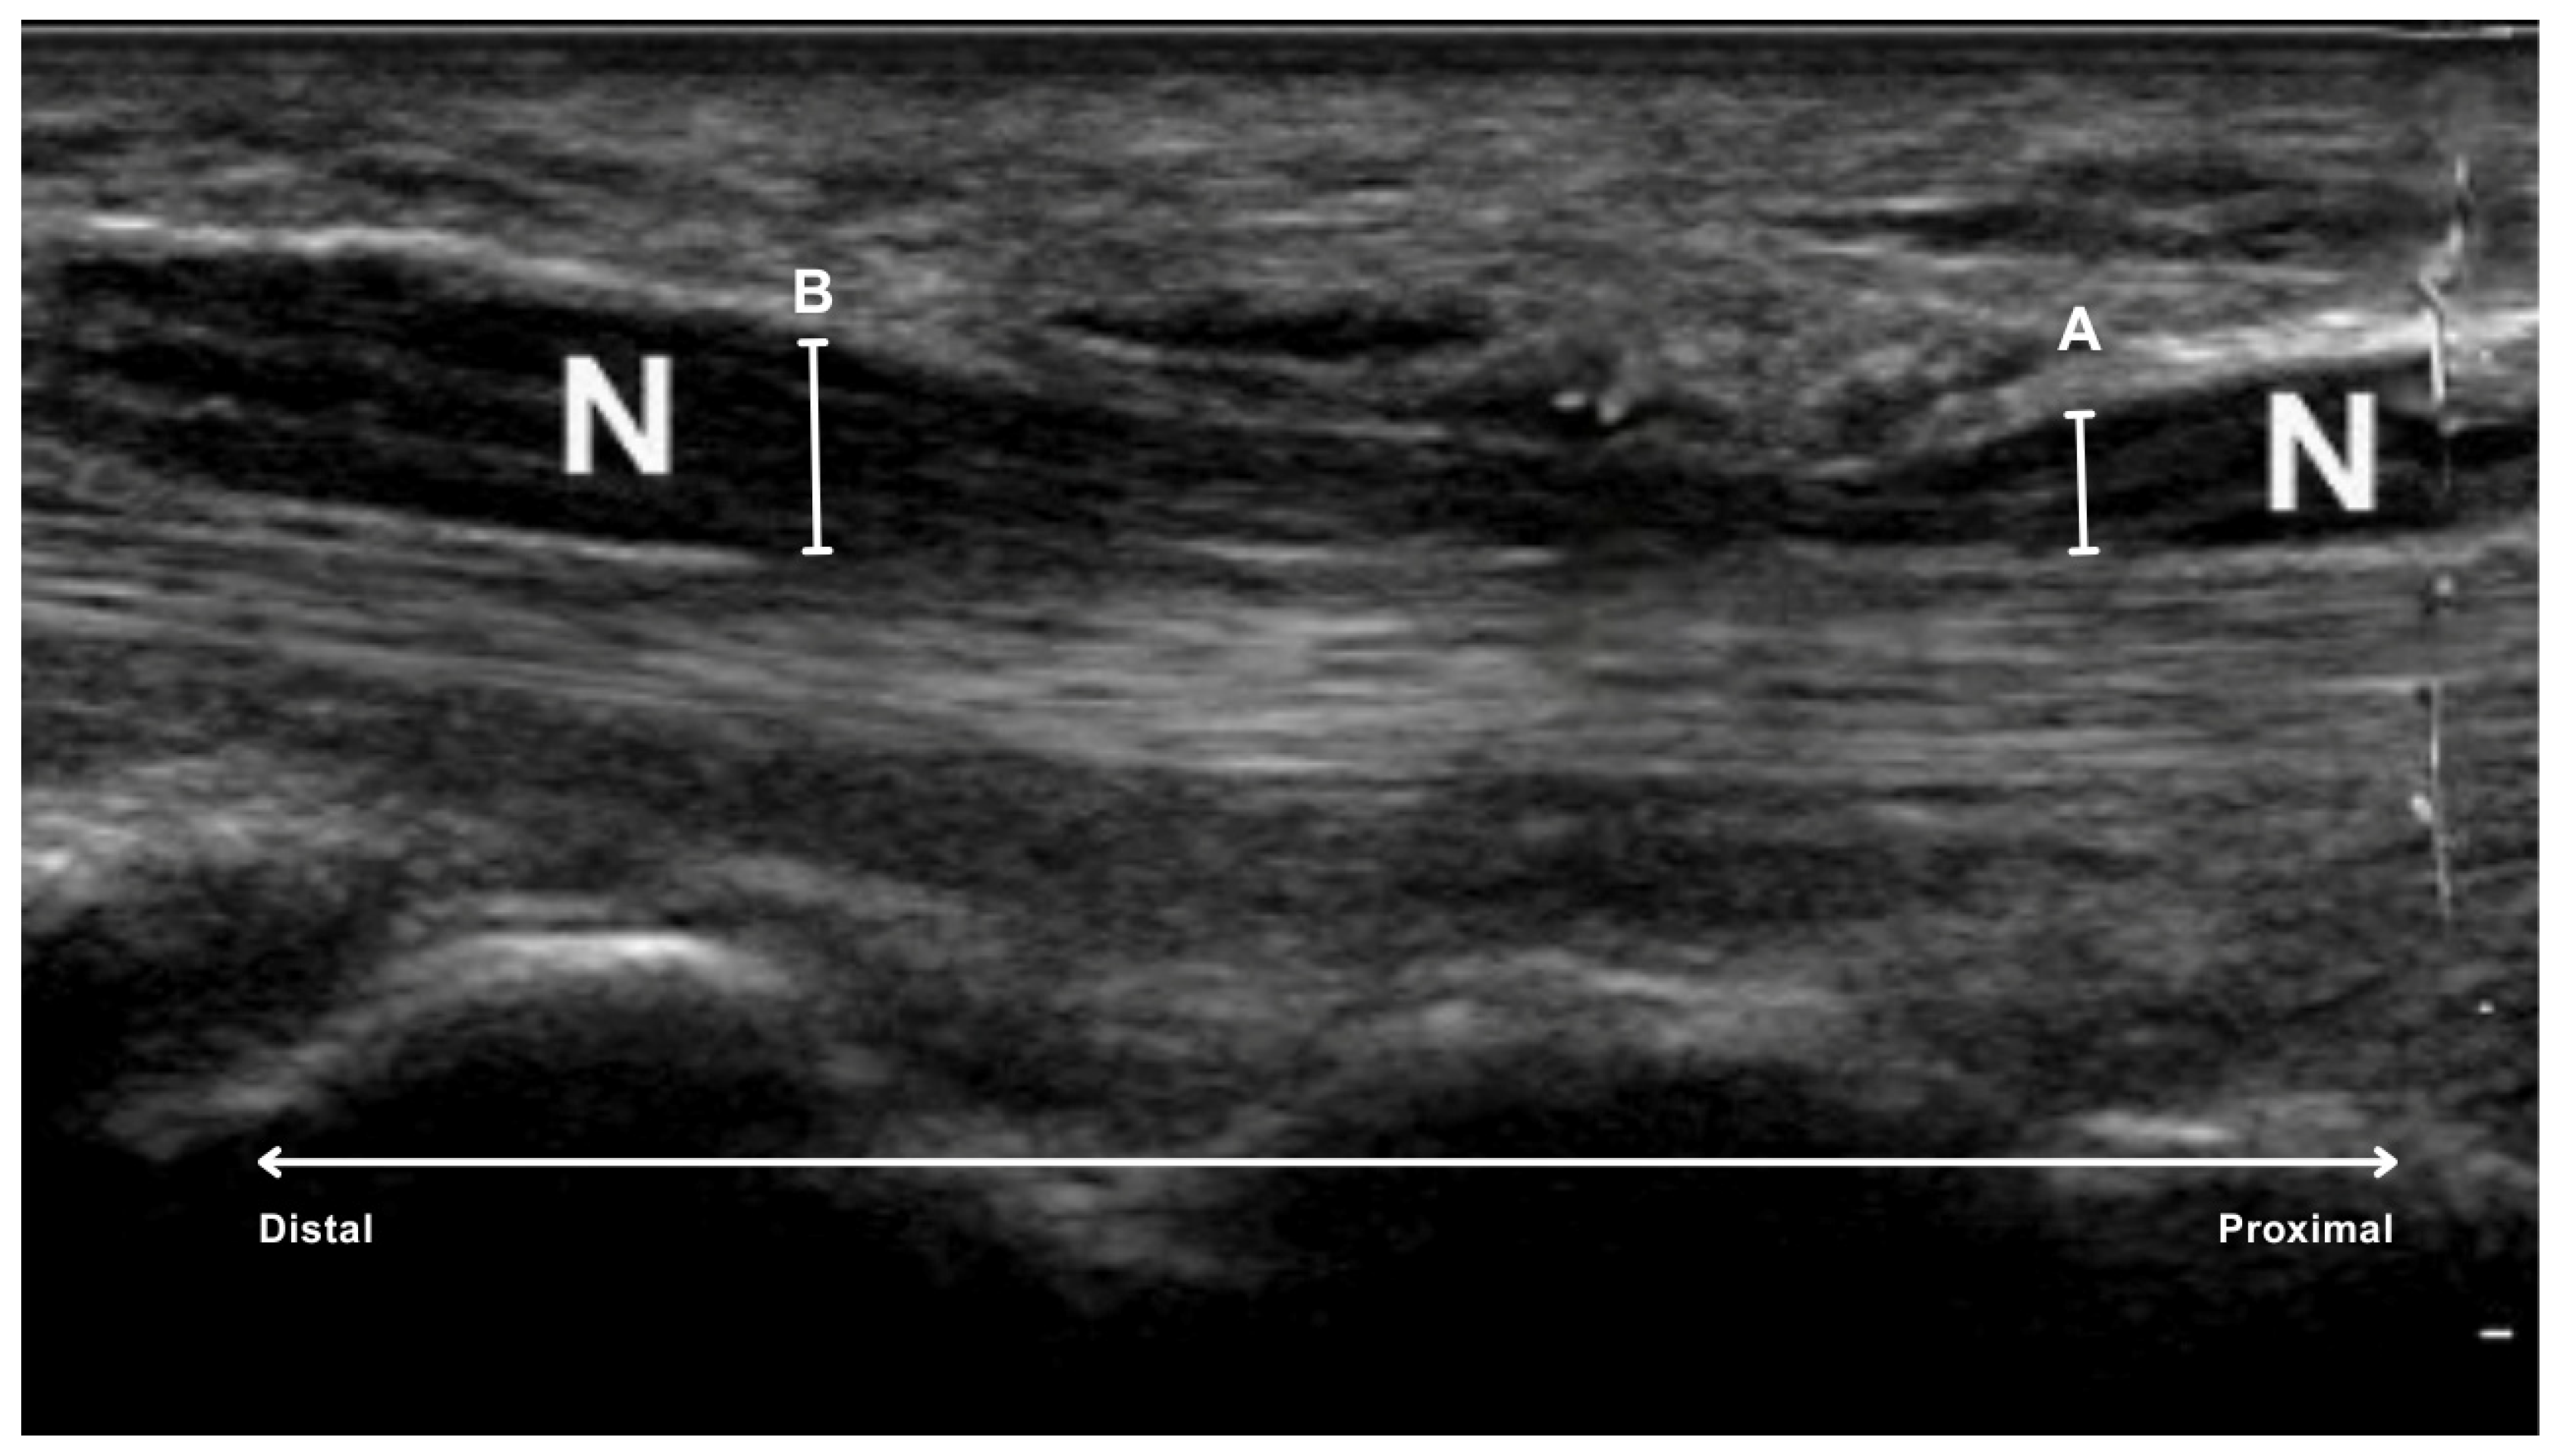

- proximal to the carpal tunnel, at the level of the first carpal row, specifically over the os lunatum, the os triquetrum and the base of the os scaphoideum (A in Figure 2).

- inside the carpal tunnel, centrally under the flexor retinaculum, at the level of the tuberosity of the scaphoid and trapezium bones on the radial side and the hamulus of the hamate and pisiform bones on the ulnar side (B in Figure 2).